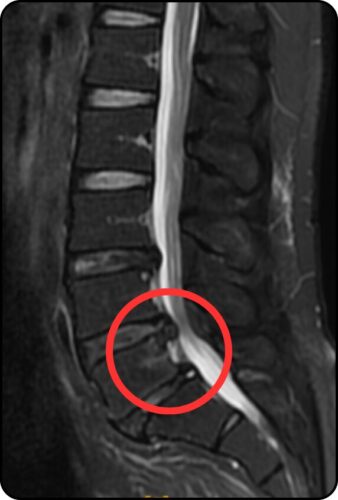

まず、こちらの写真をご覧ください。 医師にあ〜、これは痛いはずだわと言わしめた、私の腰の断面図(横から見た図)です。

赤丸の部分を見てください。 背骨の間にあるクッション(椎間板)が、後ろにボコッと飛び出しているのが分かりますか?

これが**「L4/L5 腰椎椎間板ヘルニア」**です。

飛び出した軟骨が、白い太い線(脊髄神経)をグニュッと押しつぶしています。 ライン作業で前傾姿勢になるたび、この飛び出した部分が神経に触れ、あの電気が走るような激痛を引き起こしていたんです。